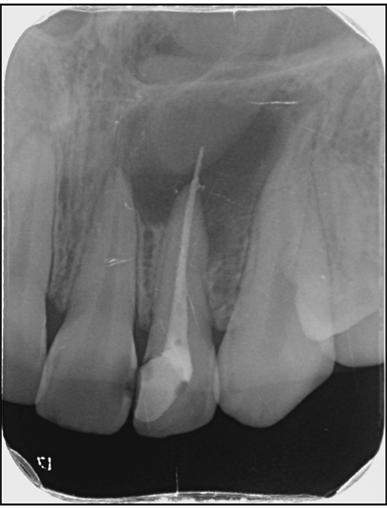

3. Evaluate the root canal treatment of tooth # 1.7?